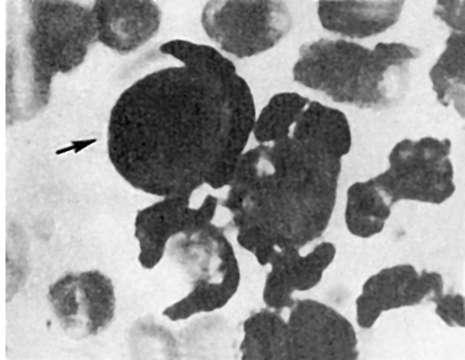

Этиология. Накопилось достаточно фактов в пользу вирусной этиологии СКВ. В эндотелиальных клетках (рис. 175), лимфоцитах и тромбоцитах крови больных СКВ при электронно-микроскопическом исследо-

Рис.

175. Системная красная волчанка. Вирусоподобные включения в эндотелии капилляра почечного клубочка (электронно-микроскопическое исследование биоптата почки). х15 000

вании обнаружены вирусоподобные включения. У больных СКВ и их родственников выявлены лимфоцитотоксические антитела, являющиеся маркерами персистирующей вирусной инфекции, и антитела к двухспиральной (вирусной) РНК. Кроме того, при СКВ находят в высоких титрах циркулирующие антитела к вирусам кори, краснухи, парагриппа и другим РНКсодержащим вирусам из группы парамиксовирусов. Однако не исключают, что вирусная инфекция при СКВ развивается вторично на фоне клеточного иммунодефицита. Большое значение имеет наследственное предрасположение.